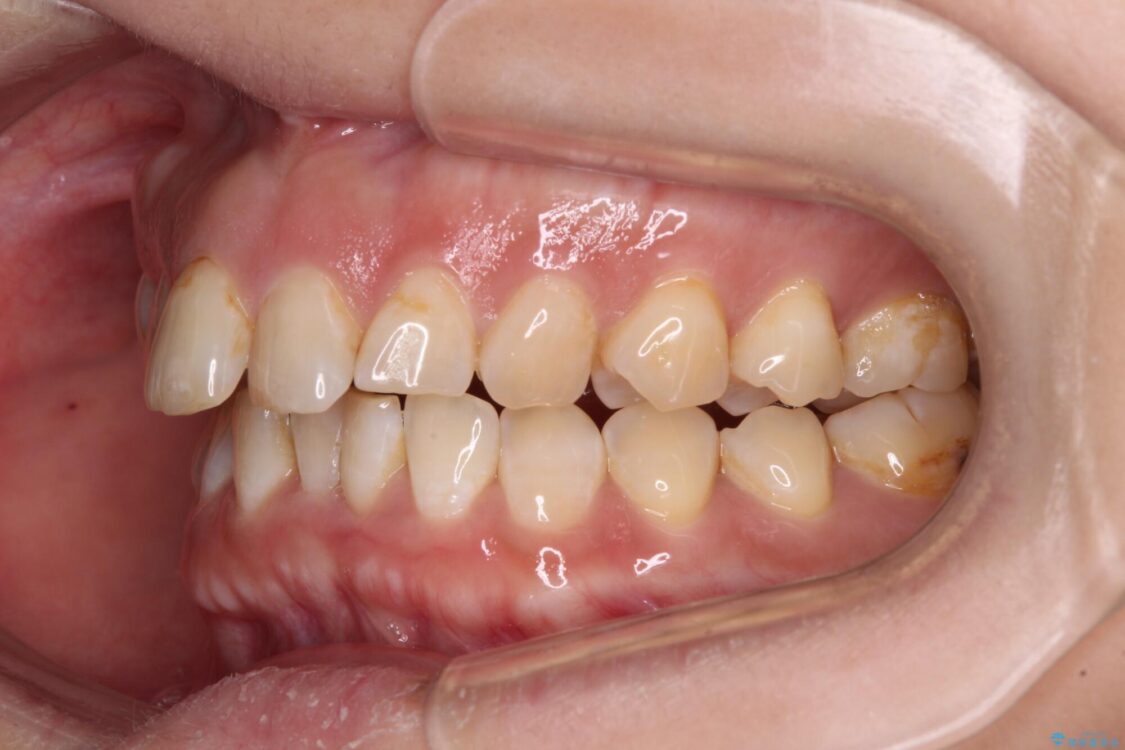

飛び出た上の前歯を気にして来院された患者様です。

奥歯の咬み合わせは、上顎歯列が理想的な一よりも数mm前方にある状態でした。

治療前

• 【モニター】飛び出た前歯を整えたい ワイヤー矯正治療 治療前画像